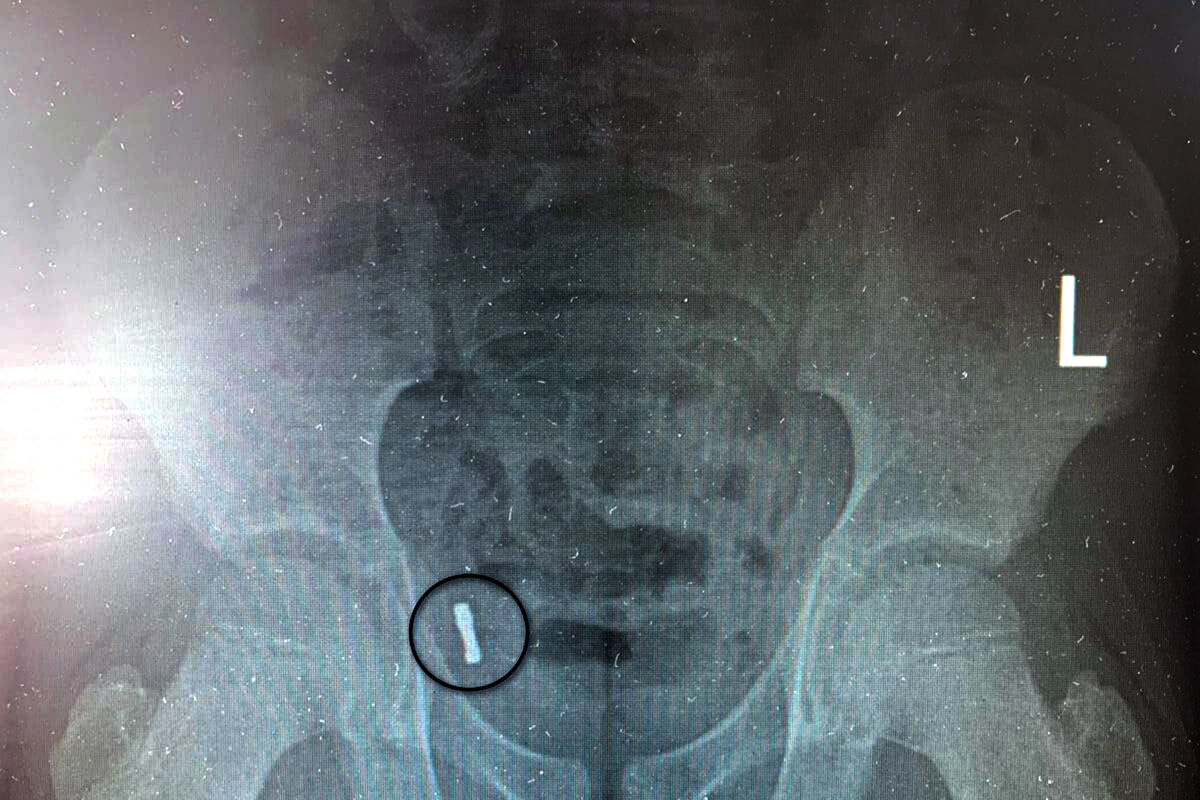

К моменту обращения за помощью инородные предметы мигрировали в аппендикс, что выявил рентген. Медики отметили, что инородные тела крайне редко попадают в аппендикс. За ребенком наблюдали трое суток, после чего приняли решение о проведении операции из-за риска перфорации и развития перитонита.

«Под общим обезболиванием медики провели ревизию брюшной полости, таким образом подтвердив нахождение магнитов в аппендиксе. Специалисты провели типичную аппендэктомию – удалили аппендикс», — рассказали в пресс-службе.